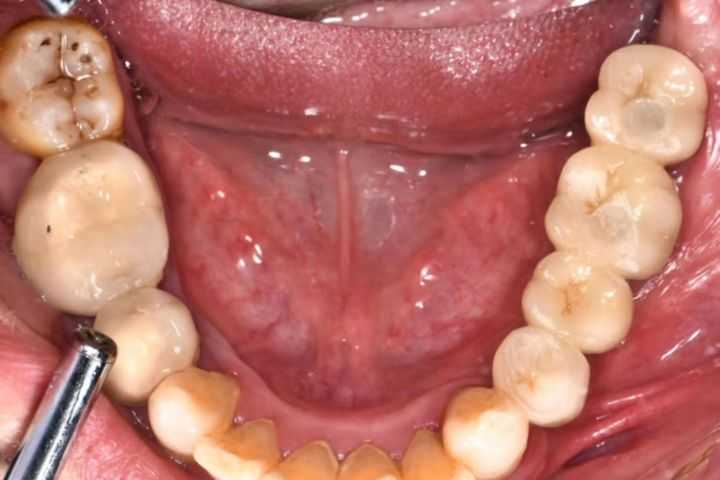

下面是一組利用種植導(dǎo)板做的種植案例:

下面這組案例,種植牙修復(fù)冠破損,拆卸后,頸部有一片粘接劑。